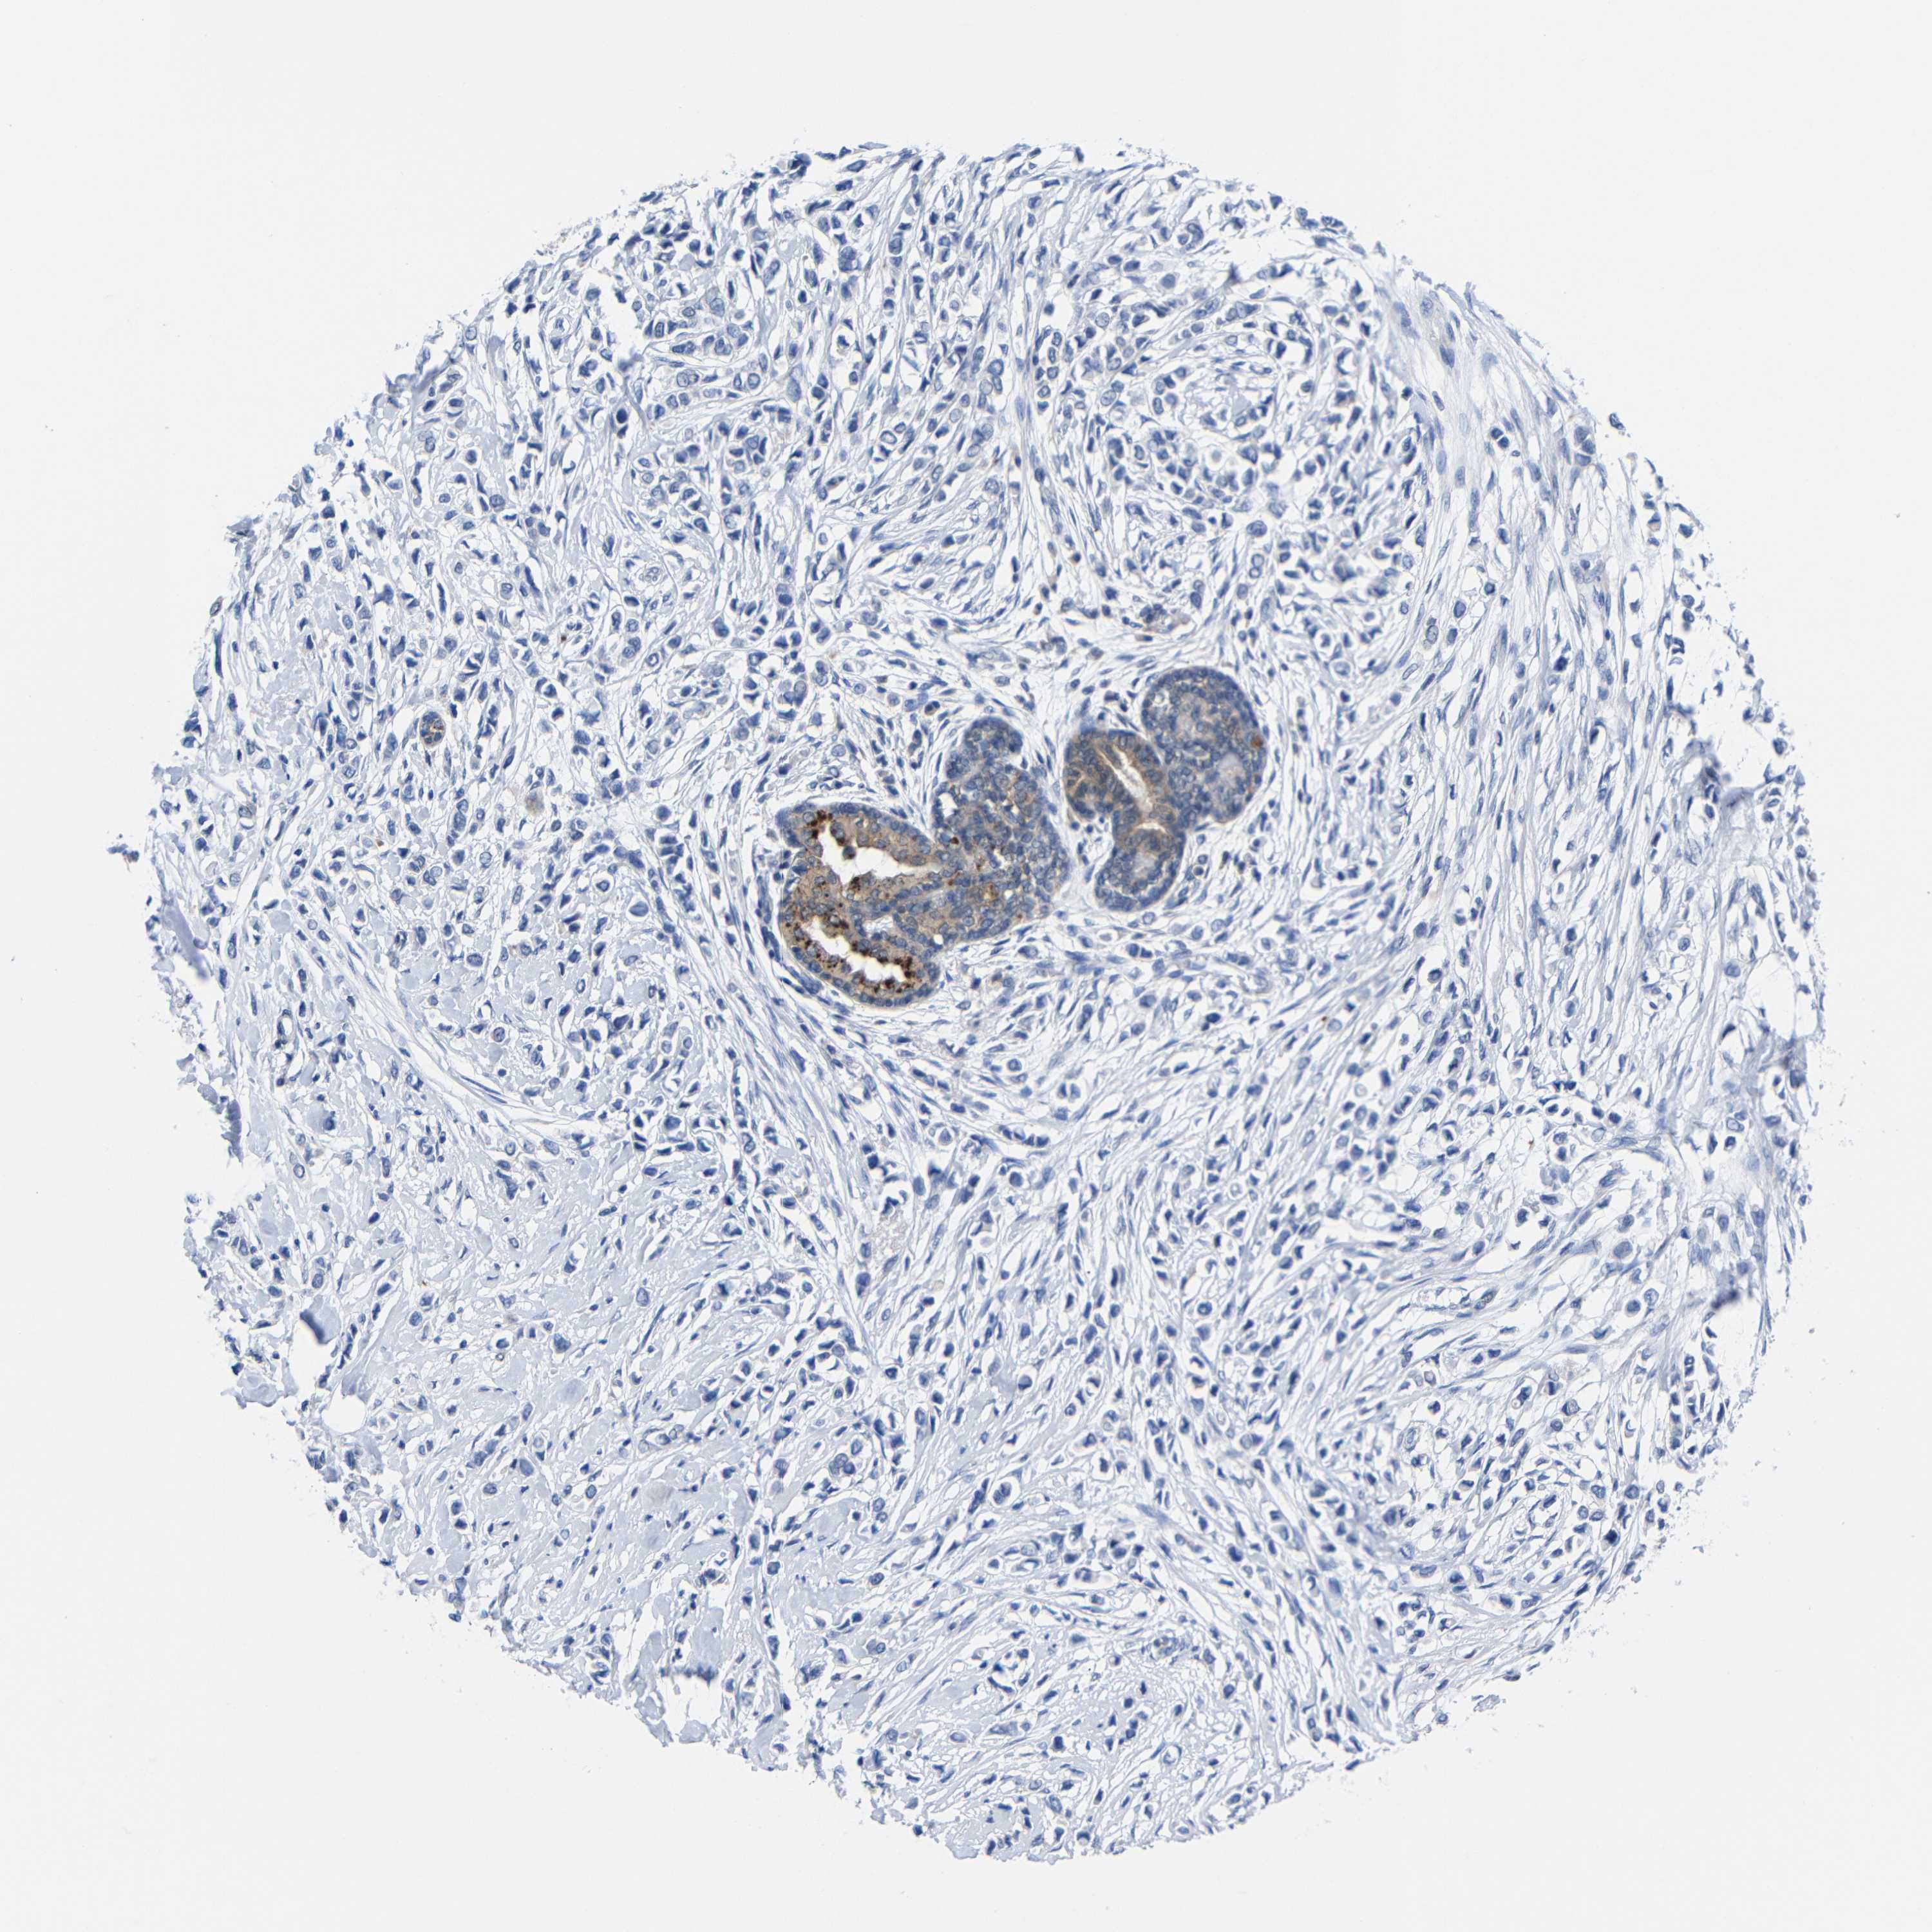

CANCER BREAST CANCER Show tissue menu

BRCA TCGA BRCA VALIDATION PROTEIN EXPRESSION

ANTIBODIES

AND

VALIDATION